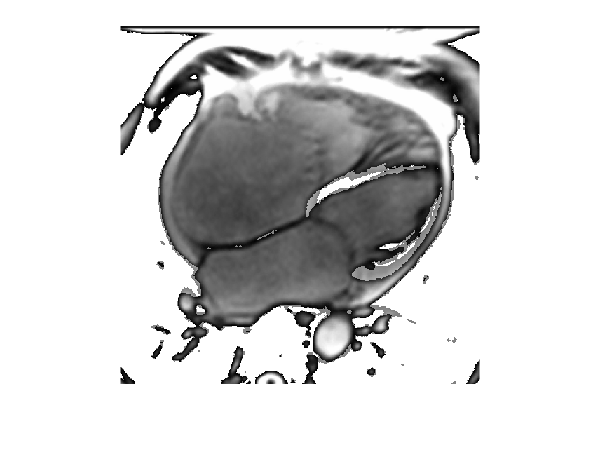

We use a sequence of cardiac MRIs from a real-time MRI video as training data. Each MRI frame is treated as a function on the domain , and the entire video as a spatiotemporal function on . For each frame, we use its pixels as training samples and select 5, 10, 15, and 20 frames from the video for reconstruction. Consequently, the total data sizes in the experiments are , , , and gridded points, respectively. Similar to the previous experiment, this is a three-dimensional dynamics reconstruction problem and we model the dynamics as a GP sample path with the following product kernel:

| (33) |

where the temporal dimension is modeled using the non-differentiable and periodic kernel since each pixel exhibits a ten-period impulse pattern, as shown in the second plot of Figure 6. For the spatial dimensions, we use the product Laplace kernel with wavelength to model the highly non-smooth MRI surfaces as shown in the right plot in Figure 6.

Due to the large data volume and the highly non-smooth nature of MRIs, RFF and Sparse GP fail to yield meaningful approximations. In contrast, KPs still produce accurate reconstructions of the real-time MRI, as shown in the second row of Figure 7. This is because KPs perform exact computations, which are essential for accurately reconstructing non-smooth functions in this experiment.